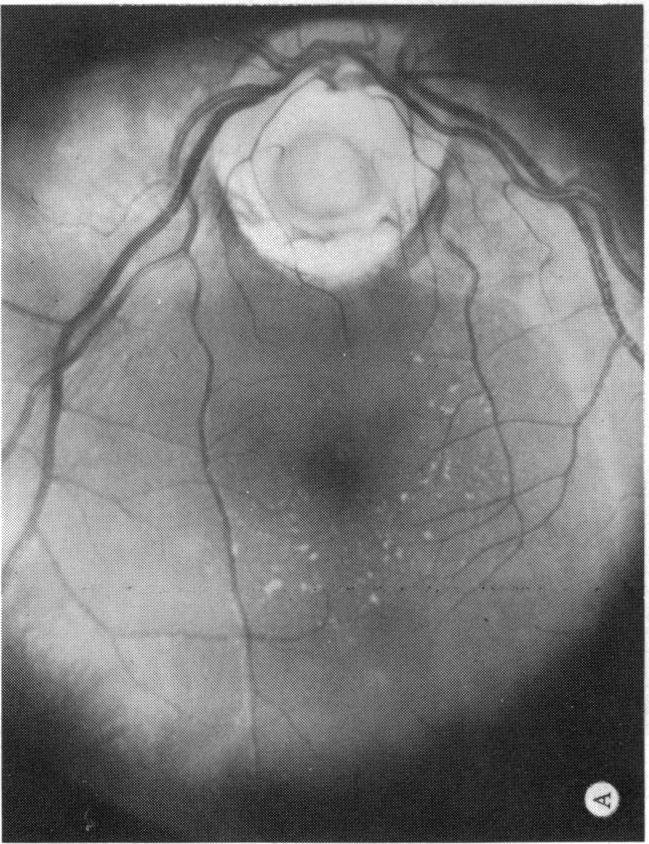

Six cases of congenital pit of the optic nervehead associated with posterior serous retinal detachment are presented. All were treated by photocoagulation along the disc margin in the area of retinal detachment. In five cases reattachment of the retina occurred, after the clinical development of a film chorioretinal adhesion at the disc margin, and appeared to be secondary to the treatment. The sixth case (Case 4), although treated, appeared to represent a spontaneous reattachment. This disorder, which frequently results in permanent decrease of central vision, affected the better, or only, eye in two of the six cases herein reported. Fluid, probably from the vitreous cavity, appears to gain access to the subretinal space via the pit. Reattachment in treated cases occurred only if an effective chorioretinal adhesion was created over the entire area of the fistulous detachment at the disc margin. Field defects after treatment appear to be secondary to either the optic pit itself or the longstanding retinal detachment, oftern accompanied by pigmentary degeneration and cystic macular degeneration, rather than juxtapapillary photocoagulation treatment.

本文报告6例先天性视神经乳头凹合并浆液性视网膜脱离。所有病例均采用视网膜脱离区域沿视盘边缘光凝治疗。5例视网膜脱离在视盘边缘形成脉络膜视网膜粘连后复位,似乎是治疗的继发结果。第6例(病例4)虽经治疗,但似乎是自发复位。这种疾病常导致中心视力永久性下降,在本文报告的6例中有2例影响了较好或仅有的一只眼。液体可能来自玻璃体腔,似乎通过视神经乳头凹进入视网膜下间隙。治疗病例中,只有在视盘边缘瘘管性脱离的整个区域形成有效的脉络膜视网膜粘连时,视网膜才会复位。治疗后的视野缺损似乎继发于视神经乳头凹本身或长期视网膜脱离,常伴有色素性变性和黄斑囊样变性,而非视盘旁光凝治疗。